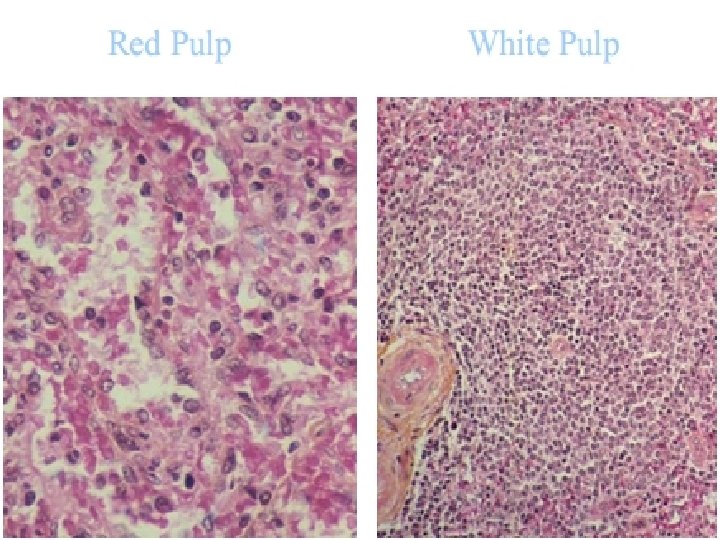

SPLEEN The largest of the lymphoid organs. Splenic pulp is composed of many erythrocytes, leukocytes, and macrophages, as well as a variety of blood vessels, all suspended within a meshwork of mesenchymal reticular cells and fibers. White pulp consists of the lymphoid tissue surrounding each of the many central arteries; it has 2 major components. The sleeves of lymphoid tissue immediately surrounding each central artery are called periarterial lymphatic sheaths (PALS). These contain mainly T lymphocytes and constitute the T-dependent regions of the spleen. Surrounding each PALS, or appended to one side, is the second component, the peripheral white pulp (PWP). PWP contains mainly B lymphocytes and usually includes a typical secondary lymphoid nodule with a germinal center.

Red pulp makes up most of the spleen and also has 2 major components: the red pulp cords and the splenic sinusoids that lie between them. The red pulp (Billroth’s) cords are irregular sheets of reticular connective tissue that branch and anastomose to surround the sinuses. In addition to reticular cells and fibers, the cords contain many cell types, including all the formed elements of blood, dendritic cells, macrophages, plasma cells, and lymphocytes. Splenic sinusoids differ from common capillaries: the lumen is wider and more irregular; there are 2 -3 - m spaces between the lining endothelial cells; and there is a sparse, discontinuous basal lamina that is composed largely of reticular fibers arranged in bands that run roughly perpendicular to the length of the vessel. The marginal zone forms a border between the white and red pulp; it consists of a moatlike arrangement of blood sinuses and loose lymphoid tissue containing few lymphocytes.